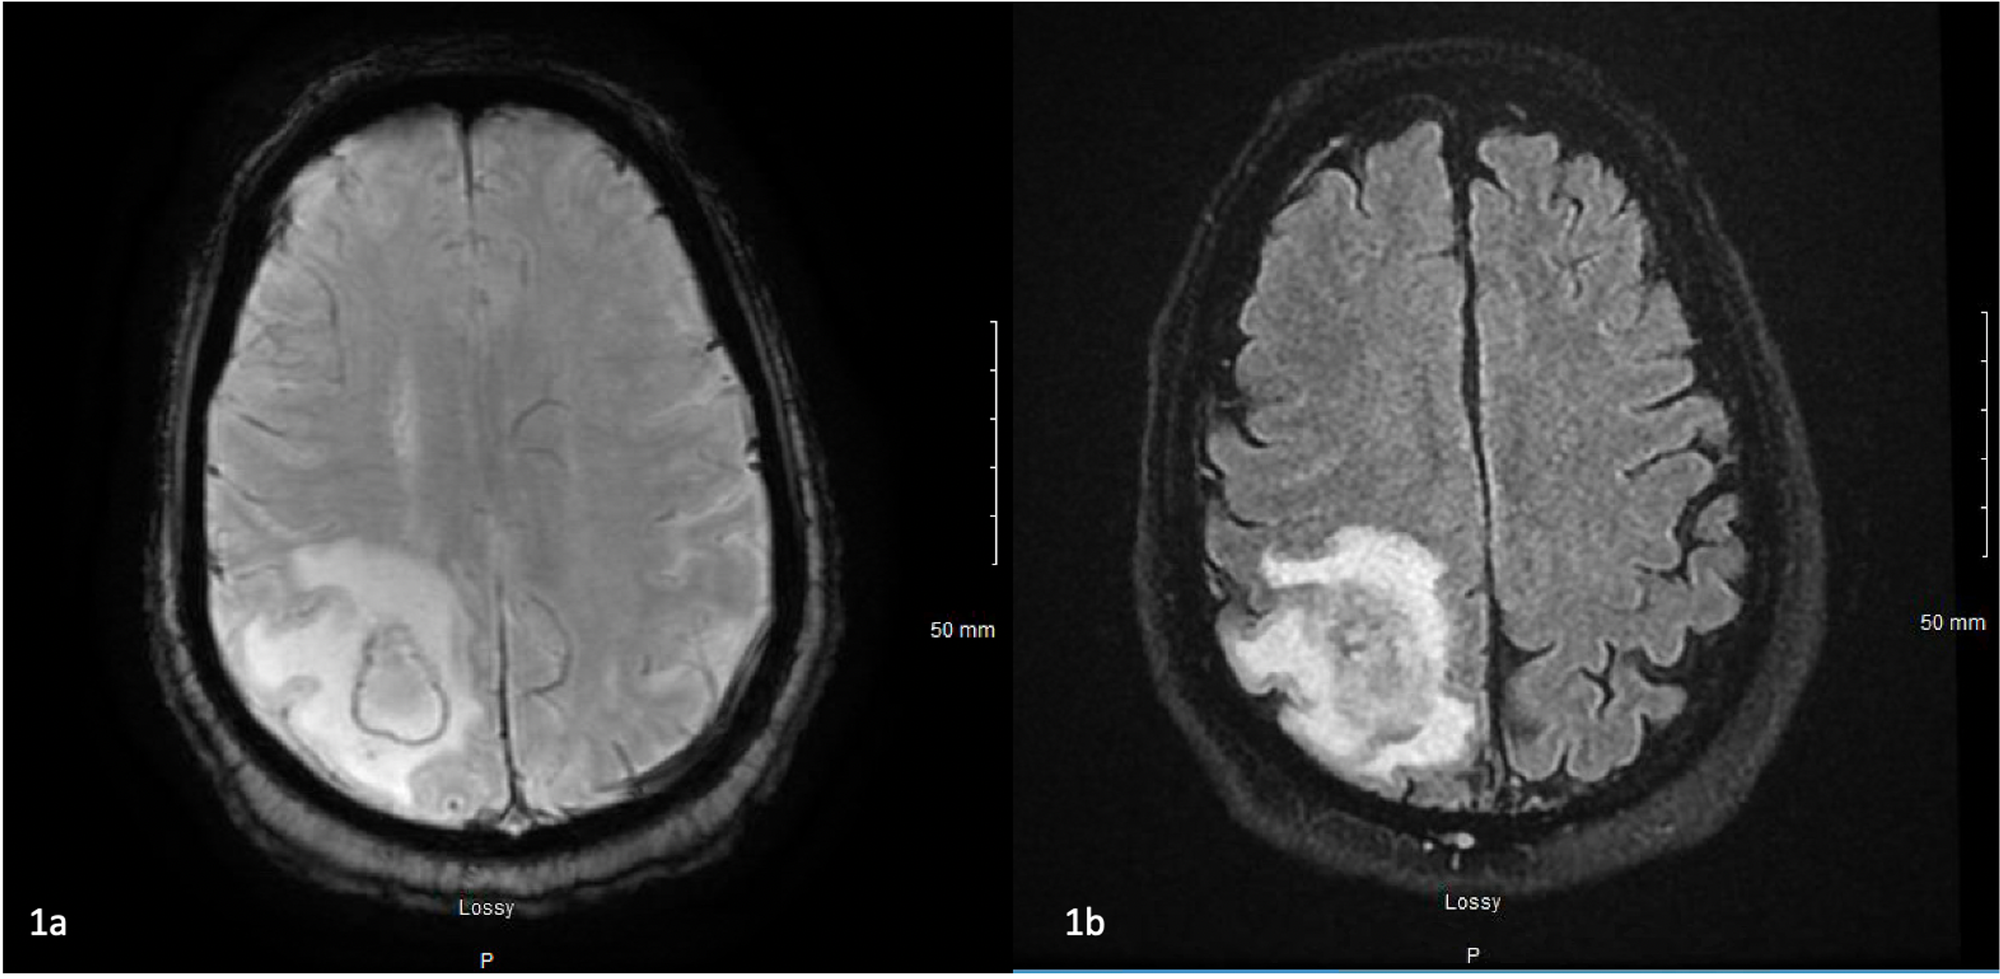

Betim GashiNokardioza është një infeksion i rrallë që fillon në mushkëri dhe më vonë mund të përhapet në lëkurë dhe tru. Ky është një infeksion bakterial i shkaktuar nga bakteri Nocardia asteroides i cili transmetohet nga pluhuri i tokës së ndotur.

Nocardia gjendet në tokë, bimësi në prishje dhe disa lëndë organike, si dhe në ujë të freskët dhe të kripur. Ai hyn në trup duke thithur ajrin në të cilin është i pranishëm bakteri, dhe gjithashtu përmes një plage të hapur. Nuk transmetohet nga njeriu te njeriu, por është më i zakonshëm te pacientët me një sistem imunitar të dobësuar për shkak të sëmundjeve të tilla si kanceri, diabeti, HIV ose AIDS.

Simptomat e nokardiozës varen nga pjesa e trupit që preket nga bakteri. Këto janë më shpesh mushkëritë, por simptomat mund të ndodhin edhe në lëkurë, sistemin e tretjes, trurin, veshkat, zemrën, sytë ose kockat.

Me këtë nokardiozë mund të ndodhë ethe, dobësi, dhimbje gjoksi, kollë, humbje e oreksit dhe djersitje natën. Gjithashtu, mund të ketë një akumulim të lëngjeve në mushkëri, por edhe pneumoni.

Në varësi të zonës së trupit, mund të ndihen shqetësime të ndryshme si dhimbje, të përziera, të vjella ose ënjtje, dhe nokardioza në tru mund të çojë në kriza, dhimbje koke ose marramendje.

Meqenëse simptomat e nokardiozës mund të tregojnë ndonjë sëmundje, do të jetë e nevojshme të bëni një seri testesh. Këto përfshijnë rrezet X të mushkërive, bronkoskopinë, biopsitë e mushkërive, trurit ose lëkurës, si dhe ekzaminimet e organeve në të cilat u shfaqën simptomat.